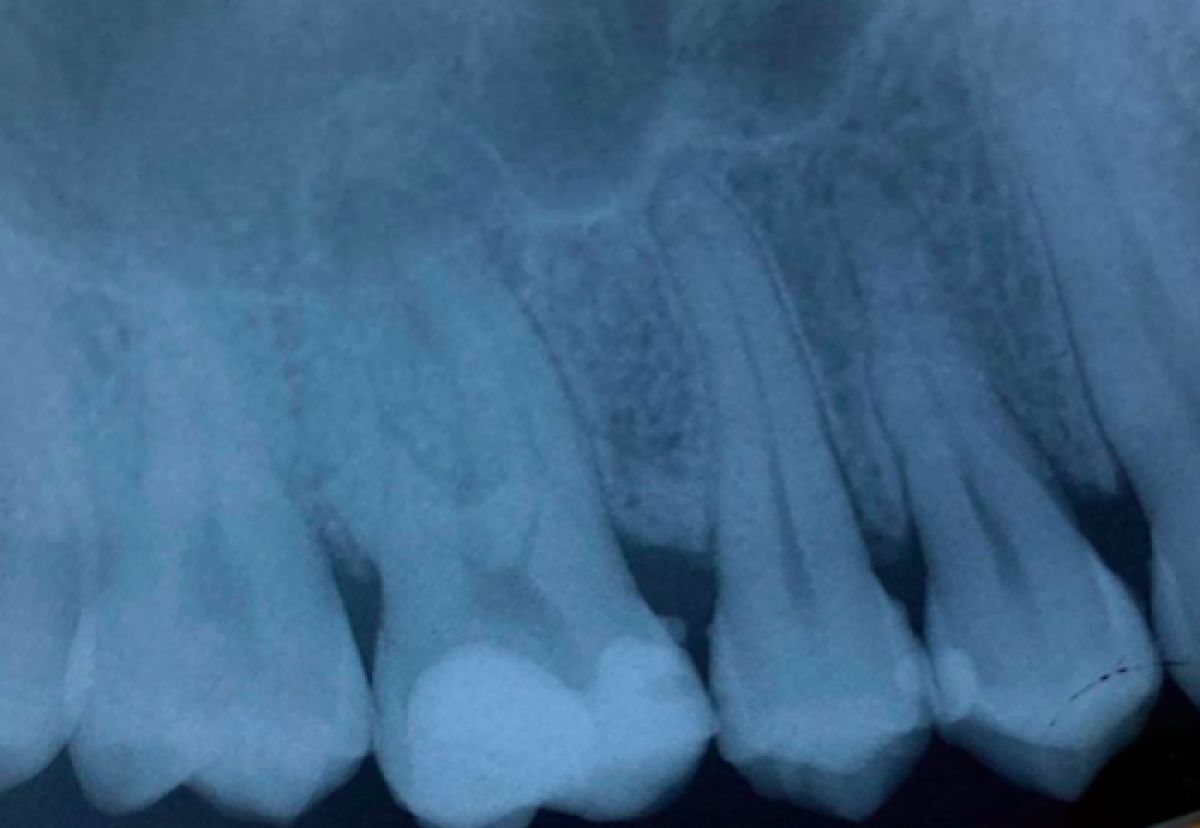

The radiographic examination (fig 2) showed the presence of periapical lesion on 1.6 and an extensive composite filling.